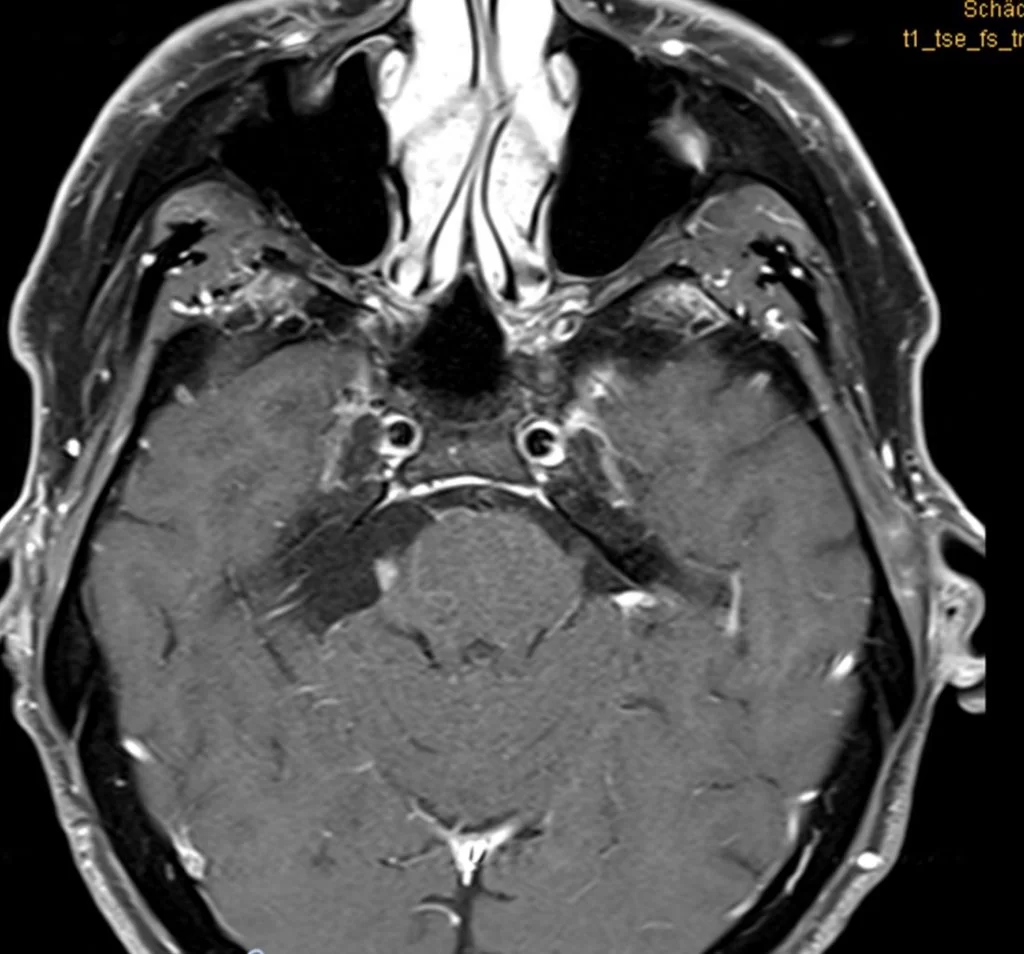

Η μετεγχειρητική μαγνητική τομογραφία εγκεφάλου δείχνει ένα εξαιρετικό αποτέλεσμα, με πλήρη αφαίρεση της βλάβης. Η ιστολογική ανέδειξε μηνιγγίωμα WHO I.

O ασθενής ανάρρωσε άμεσα και πλήρως, χωρίς νευρολογικό έλλειμα και εξήλθε του νοσοκομείου την 5η μετεγχειρητική ημέρα.